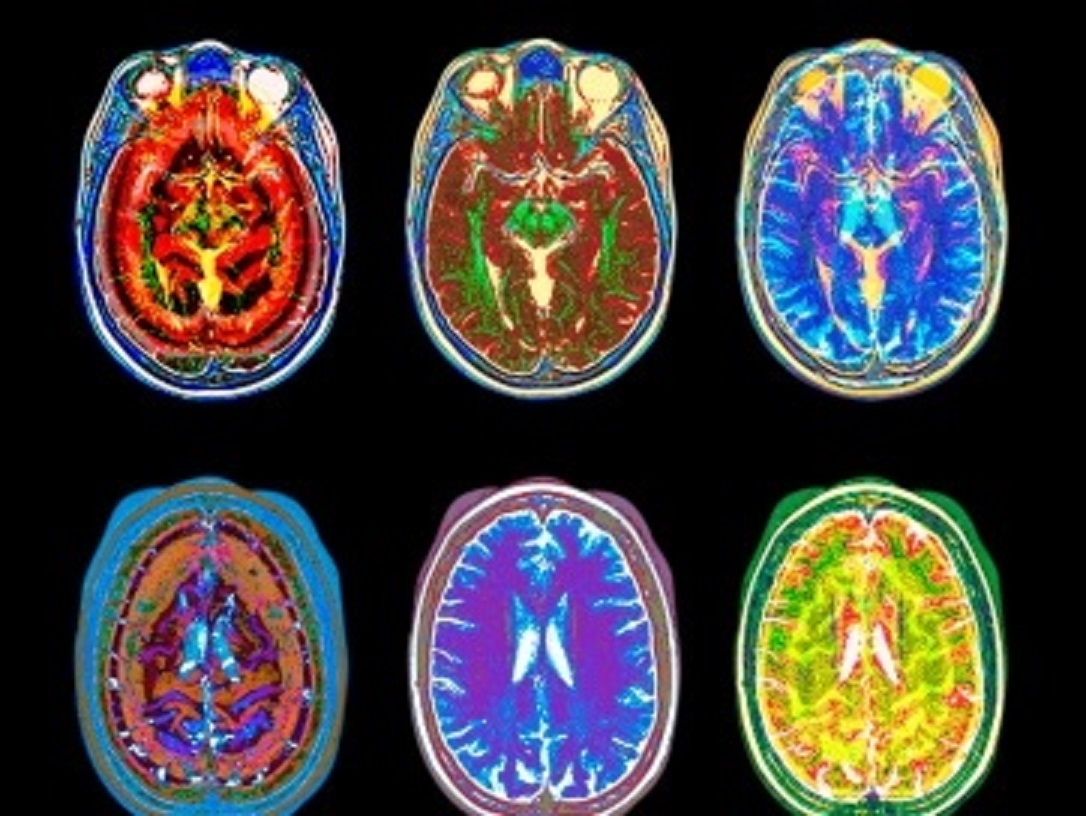

Neuroscientists are FREAKING OUT Over First MRI Scans Revealing How LSD Affects Our Brain!